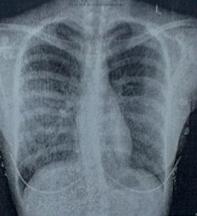

(图:魏先生到院检查强直症状)